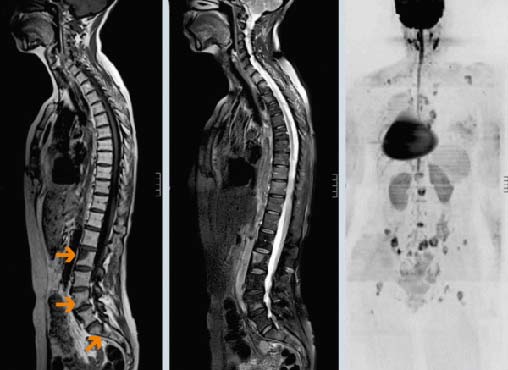

Первичные опухоли позвоночника встречаются редко. Как показывает статистика, до 90% злокачественных новообразований позвоночного столба — это метастазы рака, находящегося в других органах.

Многие типы рака метастазируют в кости, чаще всего в позвонки. В большинстве случаев опухолевые клетки распространяются гематогенно — с током крови. Вторичные очаги ослабляют костную ткань, это грозит патологическими переломами позвонков, которые приводят к сильным болям, существенному снижению качества жизни, сдавлению спинного мозга и нервных корешков.

В 95% случаев метастазы в позвоночнике являются экстрадуральными, то есть находятся за пределами твердой мозговой оболочки. Более чем в половине случаев очаги локализуются на разных уровнях позвоночного столба.

- Около 70% очагов, вызывающих симптомы, обнаруживается в грудном отделе, 20% — в поясничном, 10% — в шейном.

- В 60% случаев очаги находятся в передней части тела позвонка.

Диагностика метастазов в позвоночнике

Основные методы диагностики — КТ и МРТ. Они помогают детально визуализировать структуры позвоночного столба, опухолевую ткань. Рентгенография менее информативна, так как на снимках видны только костные структуры, обычно ее применяют при подозрении на патологический перелом.